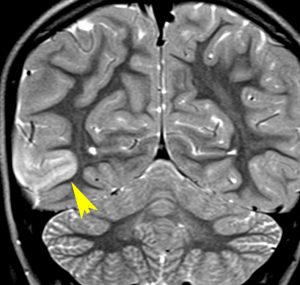

2歳時に偶然発見された,大脳皮質の限局性異形成です。10歳まで症状はでていません。

右側頭葉中側頭回の皮質が厚くなっています。T1強調画像では等信号で見づらいですが,下のフレア画像とT2強調画像では高信号になるのでわかります。

低悪性度グリオーマと間違われることがありますが,大脳皮質だけが異常な信号になっていて,皮質下白質に異常所見がないことが鑑別点です。